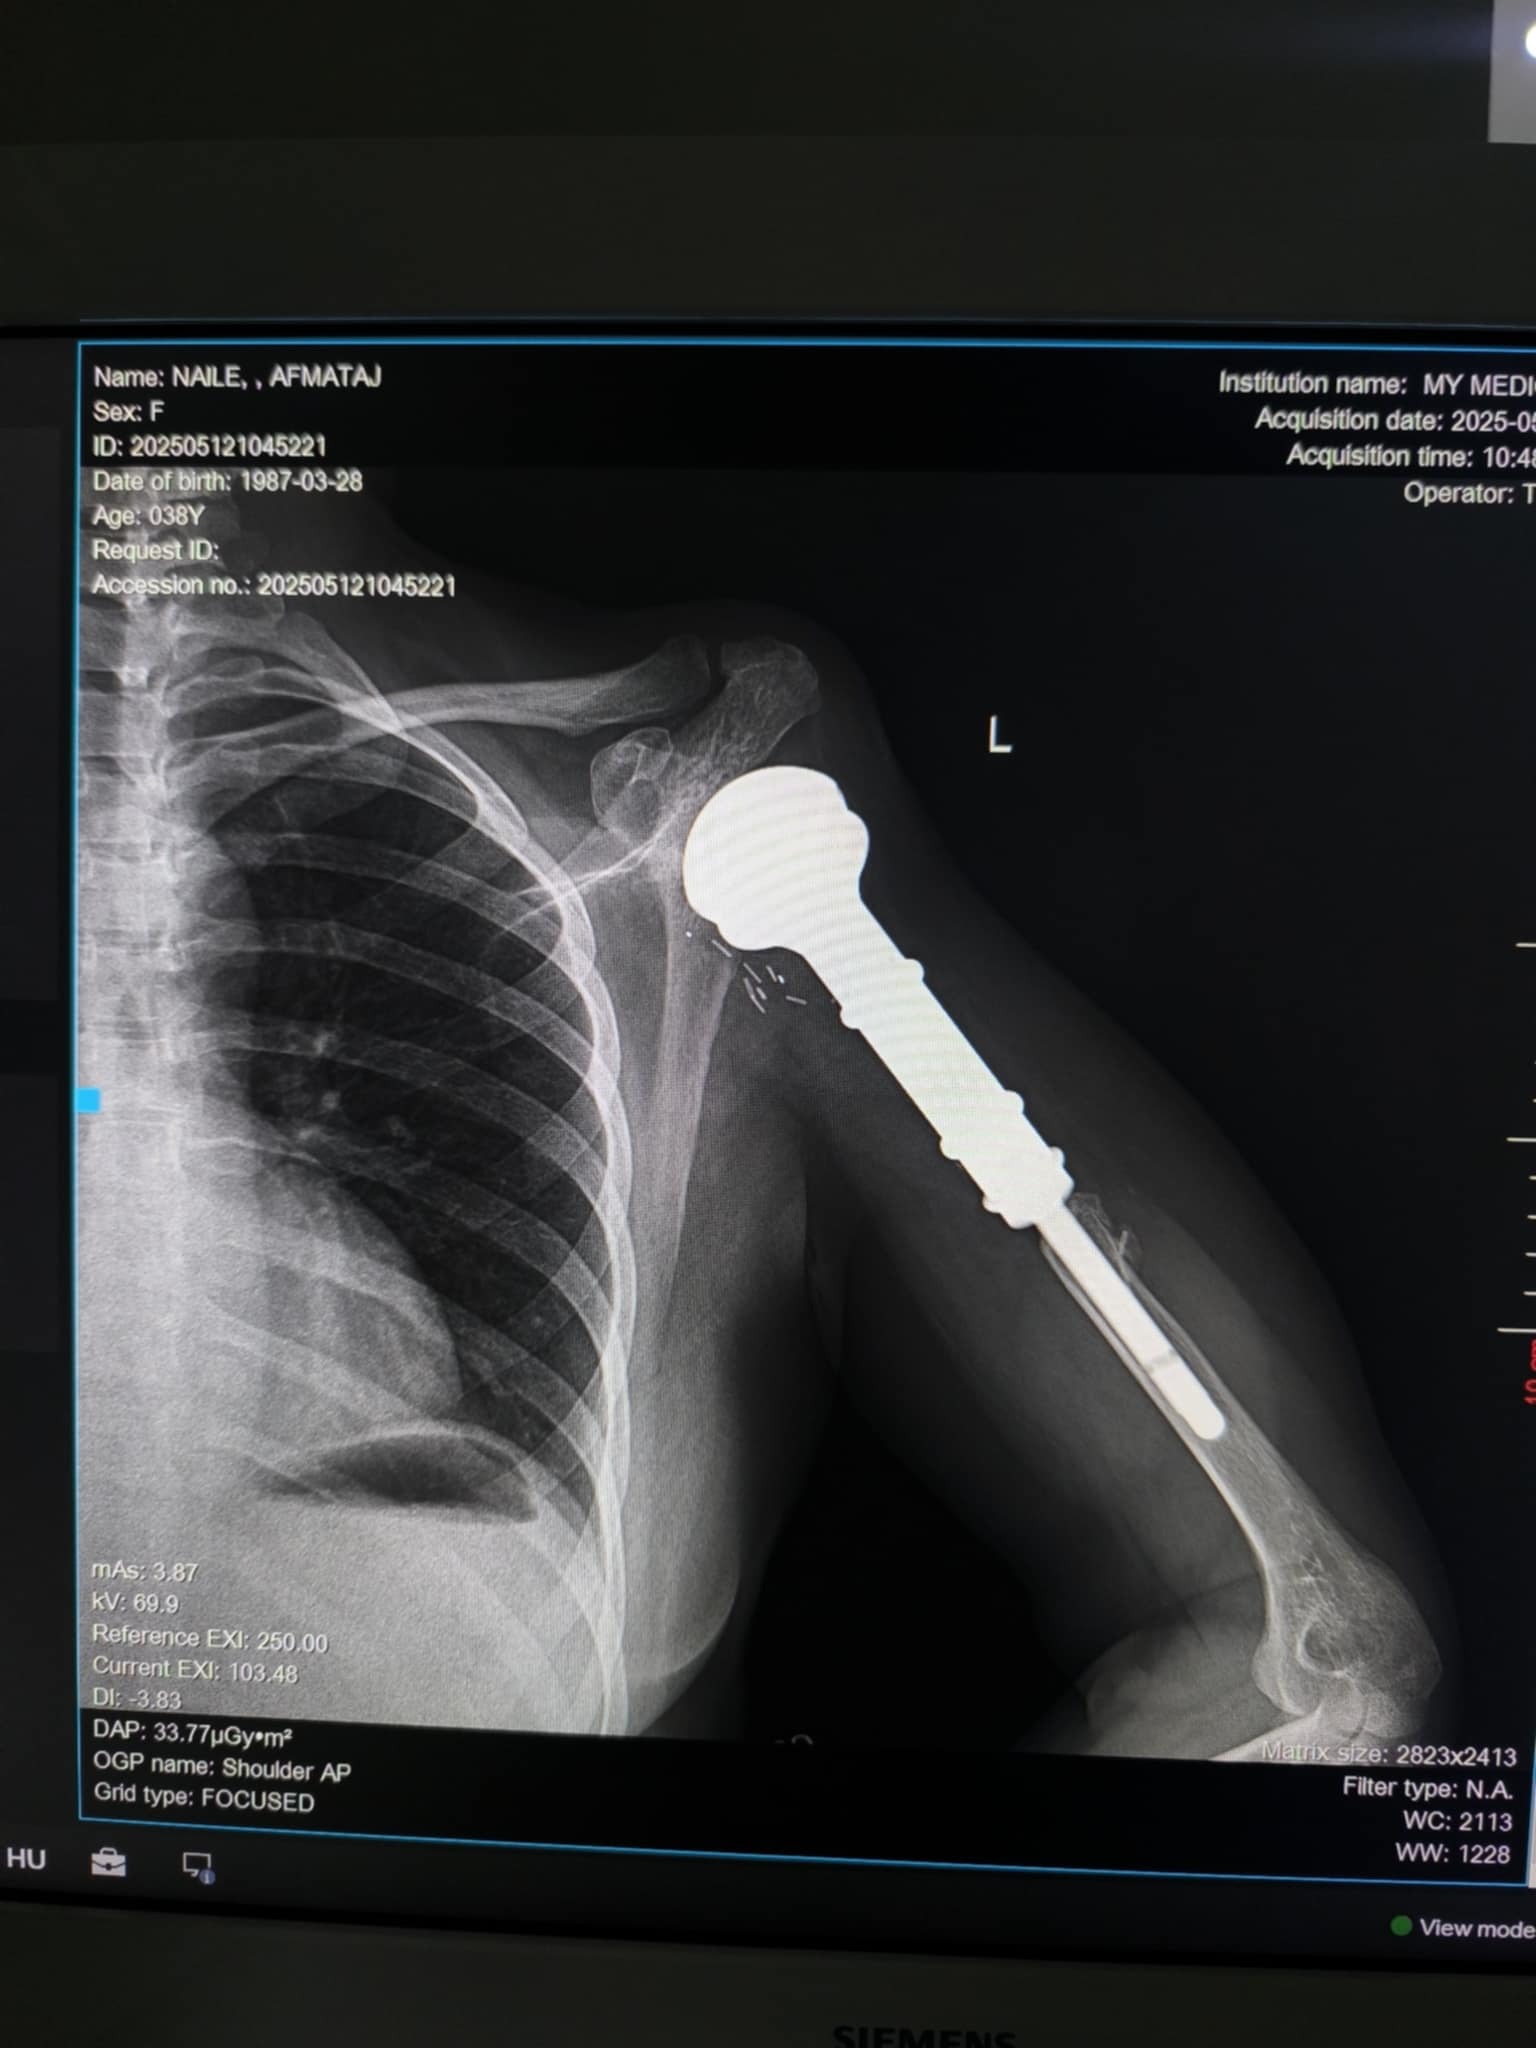

Es handelt sich um eine vierfache Mutter Naile Afmataj (Albanien) , die im Jahr 2009 aufgrund eines bösartigen Tumors im Oberarm in Deutschland operiert wurde. Damals wurde der betroffene Knochen durch eine künstliche Platte ersetzt. Um die Operation zu ermöglichen, hatte ihr Ehemann sein Haus verkauft.

Seit etwa zwei Monaten leidet die Frau unter starken Schmerzen im Oberarm. Eine aktuelle Nachuntersuchung in der Uniklinik Münster (UKM) ergab, dass die künstliche Schulter instabil ist und dringend operiert werden muss. Der Oberarzt hat eine zeitnahe Operation dringend empfohlen, da eine drohende Infektion lebensbedrohlich für die Patientin sein könnte.